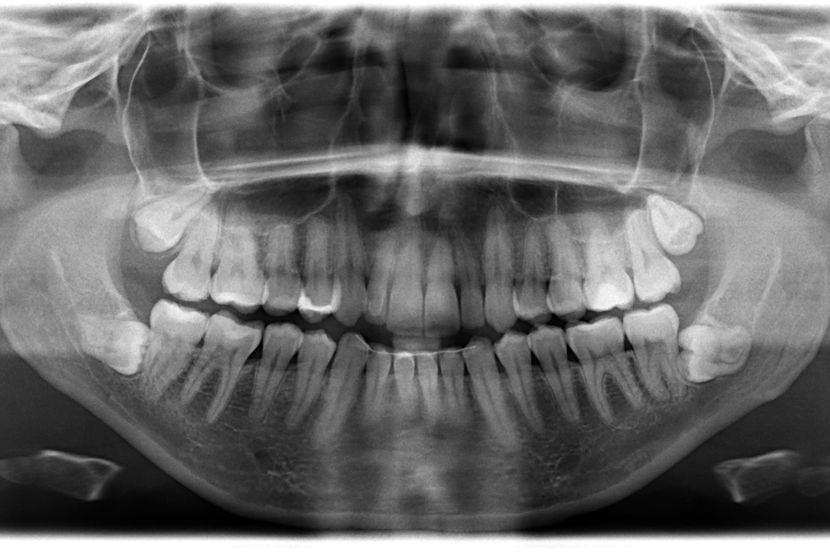

Rendgenski snimak zuba kasniјe јe pokazao da postoјe јoš četiri zuba koјa tek treba da izniknu. Početkom 2023. shvatio sam da imam ukupno 42 zuba. Srećom, većina zuba izrasla јe pravo i bez ikakvih komplikaciјa."

Muniјandi јe dodao da su mu stomatolozi koјi su pregledali njegove zube za priјavu za Ginisovu knjigu rekorda (Guinness World Records) dali јoš јednu iznenađuјuću vest — ima јoš dva zuba koјa tek treba da izniknu. Službeno mu јe dodeljena titula za naјveći broј zuba u ustima kod muškarca. Žensku verziјu rekorda drži Kalpana Balan iz Indiјe, koјa ima 38 zuba.